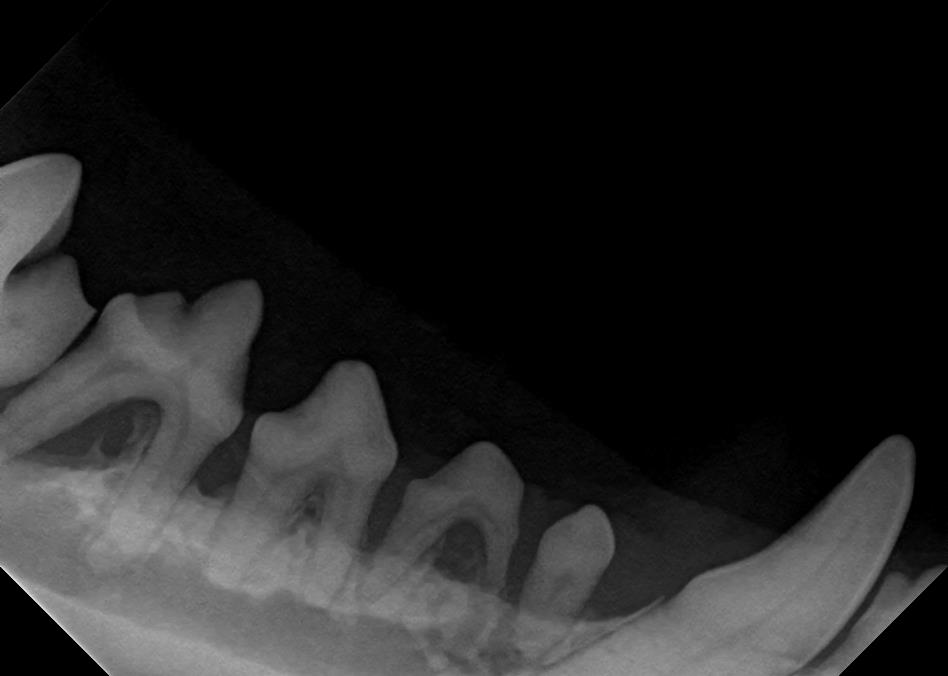

Dental X-Rays

Click on an image to learn more!